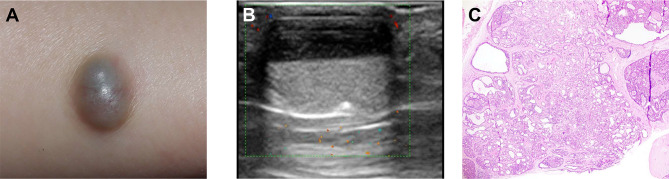

Results: The VHF features of ENH showed that the maximum diameter of the lesions was about 12.42 ± 7.66 mm. Most lesions revealed predominant craniofacial/limb involvement (62.5%) and almost all lesions (96.9%) demonstrated transdermal extension into subcutaneous tissue. Lesion morphology varied from geometric regularity (87.5%) to irregular lobulation (12.5%), reflecting ENH's structural diversity. Echogenicity patterns were classified as: homogeneous solid hypoechoic architecture (6.2%, 2/32), heterogeneous solid-dominant hypoechogenicity (40.6%, 13/32), mixed echogenicity with solid-cystic components (31.3%, 10/32, solid:cystic ≈1:1), mixed cystic-dominant echogenicity (21.9%, 7/32). Notably, the ultrasound features of inner septa, "snow falling" or "fluid-fluid level" were observed in some lesions. Additionally, 9.4% (3/32) showed intralesional calcifications and all lesions exhibited posterior acoustic enhancement. Doppler analysis highlighted vascular heterogeneity, with 87.5% (28/32) classified as Adler grade 2-3, correlating histopathologically with vascularized stromal septa.

Conclusion: The VHF ultrasound demonstrates characteristic diagnostic features of ENH, including its anatomical predilection, the involved skin layers, heterogeneous internal echogenicity, and distinctive blood flow patterns. These features provide critical indicators for differential diagnosis, establishing VHF ultrasound as a pivotal imaging modality to enhance diagnostic precision and optimize clinical decision-making in dermatologic oncology.